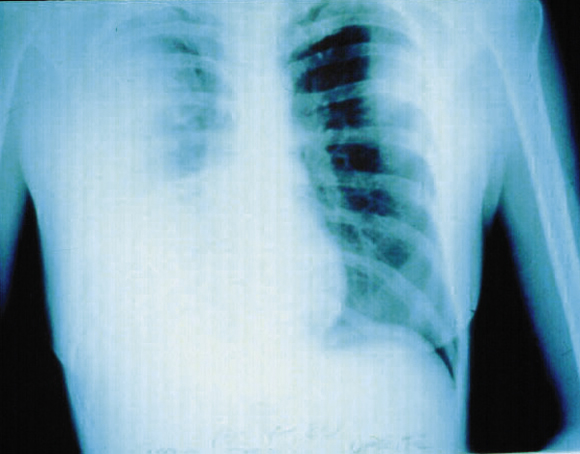

Chest x-ray may show initial segmental or lobar involvement before bronchopneumonic spread to other lobes in both lungs, which may become confluent (Box 5). Necrosis and cavitation occasionally occur early.